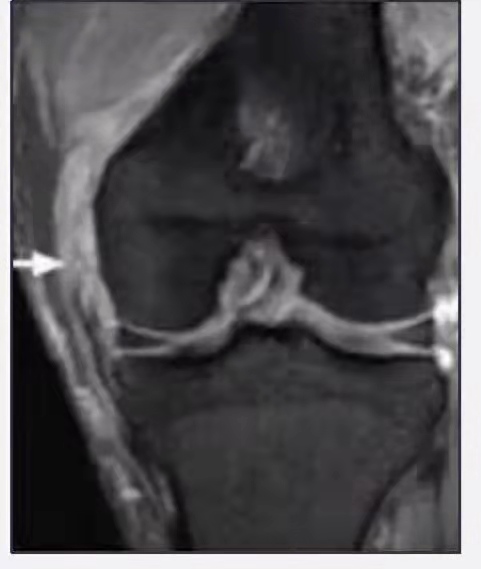

MRI检查是发现内侧副韧带损伤的首选影像学检查方法,并能判断其损伤分级。

III度:韧带完全断裂。

图6.内侧副韧带III度损伤(图片来源于网络)